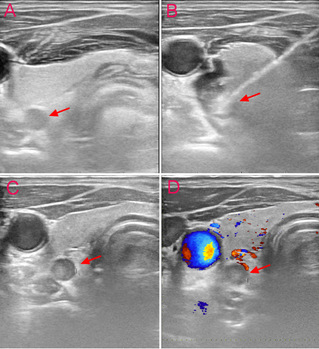

苏州九院介入科团队为该患者行局麻下甲状旁腺微波消融术,术中共消融右侧1个甲状旁腺腺体,左侧共消融2个腺体,CDFI评估消融区腺体内无血供。

△甲状腺左叶下极背侧功能亢进甲状旁腺微波消融术图:A、消融前超声;B、消融中实时超声监测;C+D、消融后超声+CDFI,提示该甲状旁腺组织消融后回声增高、无血流。(箭头所示为甲状旁腺)